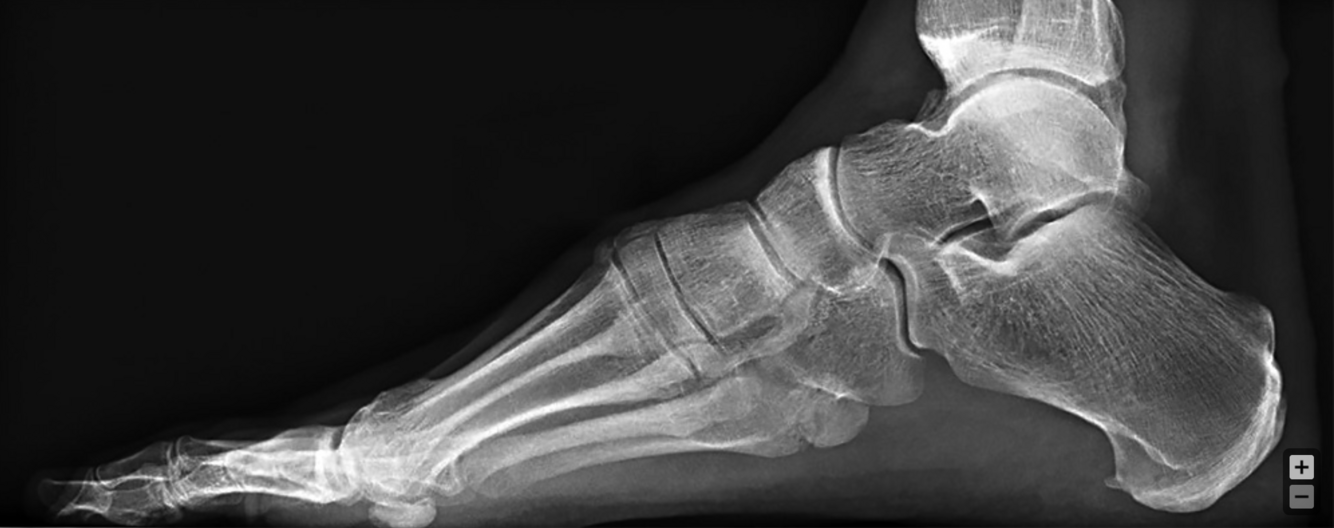

36-year-old man who has progressive wasting of his intrinsics in the hand with progressive bilateral cavovarus feet. What genetic disease is this?

36-year-old man who has progressive wasting of his intrinsics in the hand with progressive bilateral cavovarus feet. What is the sequence of weakness in his ankle/foot? How does this weakness affect the position of the foot?

1. Anterior tibial tendon - foot drop/plantar flexion

2. Peroneus brevis - foot adduction

36-year-old man who has progressive wasting of his intrinsics in the hand with progressive bilateral cavovarus feet. After weakness sets in the ankle/foot, what opposing muscles create deformation? How does this affect the position of the foot?

1. Peroneus. longus - opposition to anterior tendon. Plantar flexes first ray.

2. Posterior tibial tendon - opposition to the peroneus brevis. Adduction of foot.